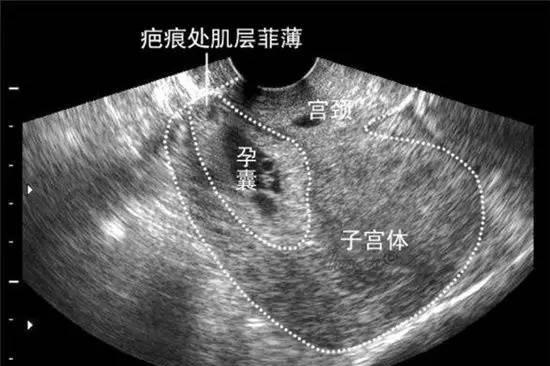

宫角孕的情况一般情况是移位妊娠的情况。考虑一般情况怀孕4个月左右,宫角妊娠随妊娠进展,其妊娠结局有三种:孕囊停止发育,致流产;孕囊在宫角处向外扩展,使宫角膨胀外突,最终导致宫角破裂;亦可向宫腔扩展,妊娠可延至晚期而自然分娩。因宫角部肌层组织薄,又是子宫血管与卵巢动静脉及输卵管血管吻合处,血运丰富,孕囊种植在此,可随着妊娠进展出现肌层破裂,出血甚多,若诊断延误可危及生命。所以说,宫角妊娠一般在四个月左右会破裂。